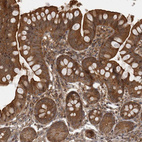

Immunohistochemical staining of human liver, skin, small intestine and testis using Anti-STK24 antibody HPA026435 (A) shows similar protein distribution across tissues to independent antibody HPA026502 (B).